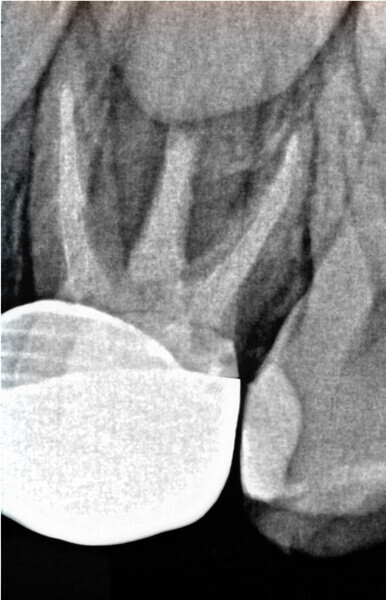

Fig. 6: Post-op radiograph. (Image: Dr Anne Heinz)

Overall, the affected tooth was prepared quickly and reliably with the aid of the fully automated co-pilot—a true blessing, since compliance during treatment, supported by a reduced treatment time through a reliable workflow, is important, particularly with (young) anxious patients. In combination with a child-friendly and relaxing environment, this set-up eliminates much of the original trepidation, even in the case of an endodontic treatment. After extensive irrigation of the canal with sodium hypochlorite and drying of the canals with the appropriate paper points, the canals were filled with calcium hydroxide and a ceramic paediatric crown was inserted adhesively for restoration. After checking the occlusion and articulation, the patient was discharged satisfied and pain-free (Fig. 6).